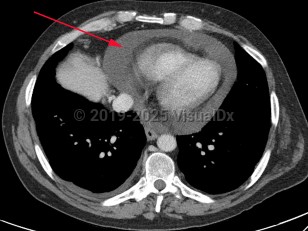

Pericardial effusionPericardial effusion

Pleural effusionPleural effusion

Pulmonary edema